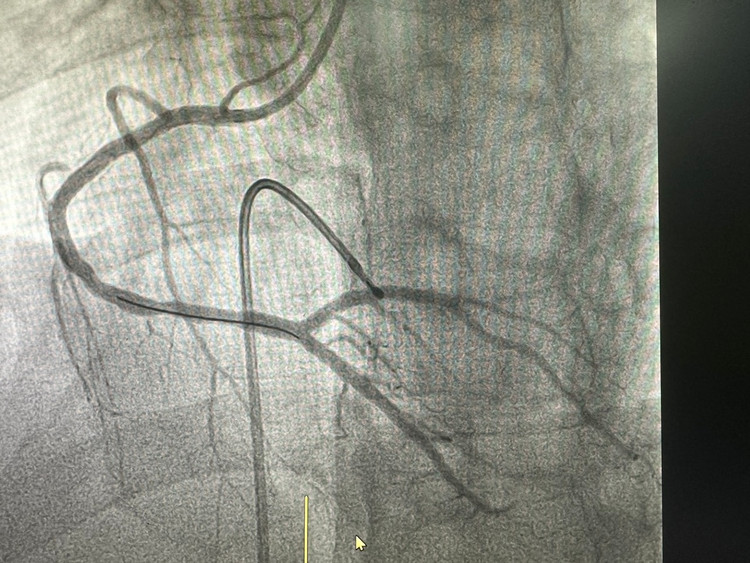

Chụp động mạch vành qua da cho hình ảnh hẹp 95%RCA(p),70%LCX(p),80%OM(p). Bệnh nhân được tiến hành đặt máy tạo nhịp tạm thời chủ động kết hợp can thiệp động mạch vành.

Bác sĩ Piter cùng cộng sự khoa Tim mạch đã thành công đặt 01 stent vị trí RCA(p), sau can thiệp chụp kiểm tra dòng chảy tái thông tốt, BN không còn đau ngực, huyết động ổn định, đã được chuyển về khoa Tim Mạch theo dõi và điều trị.